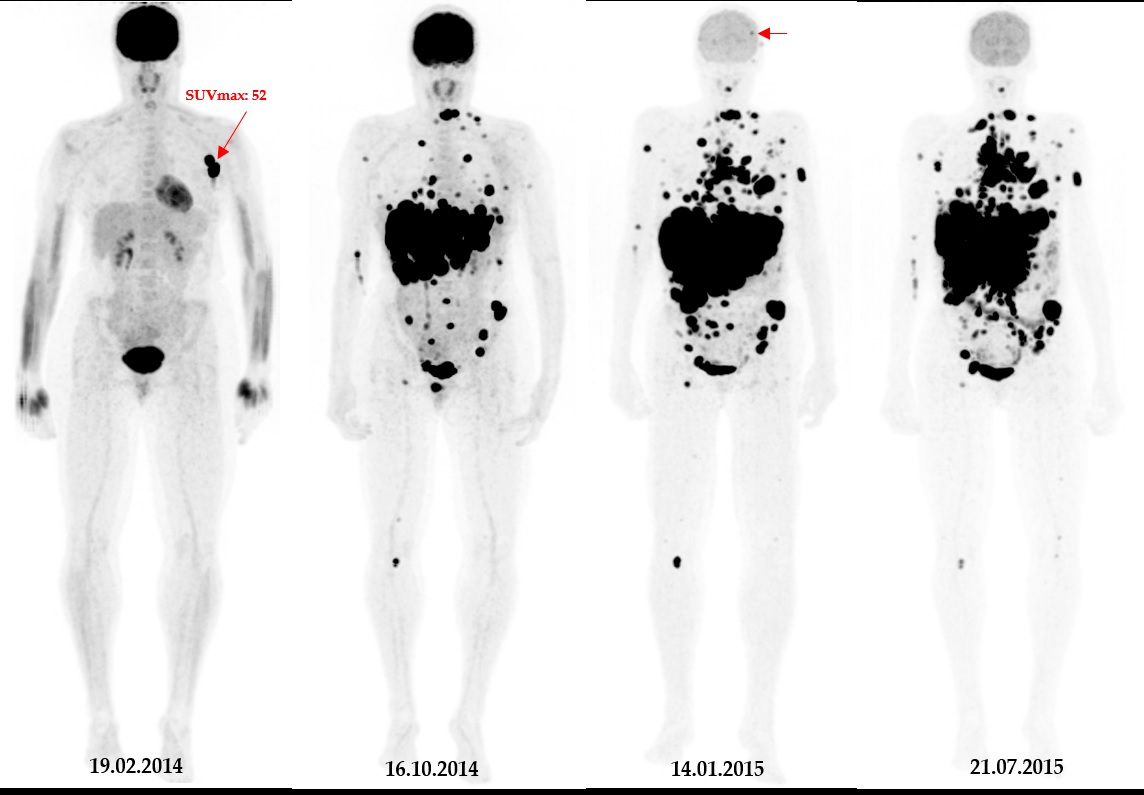

InHealth will soon launch what the company is calling the UK's first relocatable radioligand therapy service for cancer care.

InHealth said its existing PET-CT service already supports over 20,000 UK cancer patients each year through both mobile and static sites. The company said the relocatable facility to be offered with its new radioligand service will provide additional capacity to existing sites that offer this kind of care from acute hospitals and static locations.